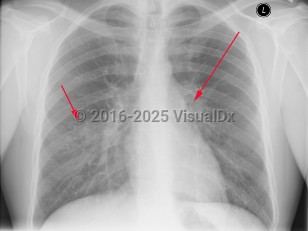

Tuberculosis in Child

The tubercular bacilli from the infective droplet are taken up by the alveolar macrophages, particularly in the upper and mid-lung zones, which have the highest air flow rates. The breach of the bacteria into the subpleural interstitium causes a local inflammation and consolidation with an exudate and cellular infiltrate. This hallmark of primary pulmonary infection is called the Ghon focus. The bacilli are then rapidly taken up by the mediastinal lymph nodes (hilar and/or paratracheal), resulting in their enlargement and liquefaction, which liberates bacilli that can spread hematogenously throughout the body, seeding different organs. The Ghon focus and the mediastinal lymph node enlargement form the primary or Ranke complex. In most patients, the infection remains latent, being forever contained by the development of cell-mediated immunity that results within 3 weeks to 3 months in a positive skin (tuberculin) test. However, in 5%-10% of patients, mostly within 2-3 years, this initial infection evolves toward active TB. This progression is more common in immunosuppressed states such as AIDS and in children younger than 5 years. While pulmonary TB is the most common form of TB in adults and children, extrapulmonary TB can occur in any age group, although it is more common in younger age groups (eg, tuberculous lymphadenitis).

Symptoms of pulmonary TB are nonspecific and include anorexia, fatigue, anemia, weight loss, fevers, and night sweats. Cough is usually productive, and hemoptysis may occur. Pleural involvement may lead to chest pain and dyspnea. Physical examination findings include rales and signs of consolidation. Auscultation over cavities may reveal amphoric breath sounds (like the sound made by blowing across the mouth of a jar). Signs of pleural effusion may also be found. Pericarditis and pericardial effusion can occur.